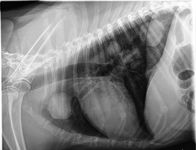

The anatomical location and histologic subtype of primary pulmonary tumors in dogs tend to share similar distribution patterns observed in people. Adenocarcinomas usually present as peripheral, solitary, well-defined masses (Figure 1), while bronchoalveolar carcinomas often manifest as peripheral multifocal densities (Figure 2).5,12,14,18 And primary lung squamous cell carcinomas tend to grow as solitary, hilar masses.10,12,14,18

2. A lateral thoracic radiograph of an 8-year-old spayed female Labrador retriever presented for evaluation of a decreased appetite and lethargy of four weeks' duration. Multiple soft tissue opacities affecting the pulmonary parenchyma are identified, which were cytologically consistent with bronchoalveolar carcinoma. (Photograph courtesy of Dr. Laura Garrett.)

The appearance of primary lung tumors varies from a solitary mass (Figure 1) to involvement of an entire lung lobe or multiple lobes (Figure 2), indicating metastatic disease or multicentric pulmonary tumors. Radiographic assessment may be confounded by atelectasis secondary to pneumothorax or pleural effusion. Pleural effusion may result from regional lymph node metastasis, extension of the tumor into the pleura, or concurrent disease such as congestive heart failure or other nonneoplastic processes such as hypertrophic cardiomyopathy, feline infectious peritonitis, and chylothorax.1,14 But keep in mind that pleural effusion devoid of neoplastic cells on cytologic examination does not necessarily rule out primary pulmonary neoplasia.14,19,28